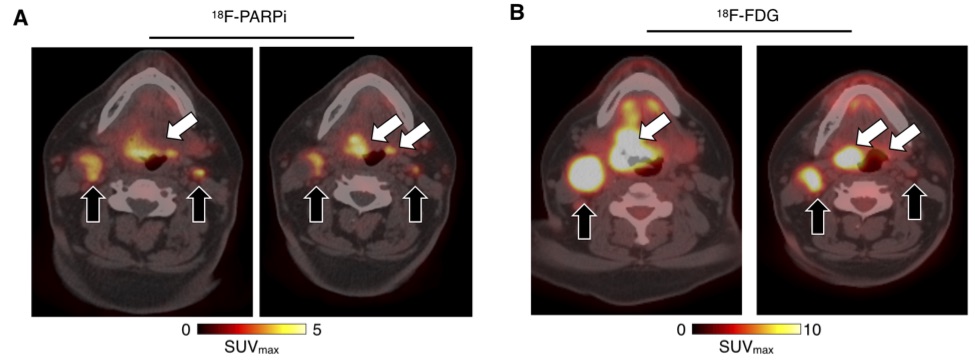

Background: We report preclinical and first-in-human-brain-cancer data using a targeted poly(ADP-ribose)polymerase1 (PARP1) binding PET tracer, [ 18F]PARPi, as a diagnostic tool to differentiate between brain cancers and treatment-related changes.

Methods: We applied a glioma model in p53-deficient nestin/tv-a mice, which were injected with [ 18F]PARPi and then sacrificed 1 hr post-injection for brain examination. We also prospectively enrolled patients with brain cancers to undergo dynamic [ 18F]PARPi acquisition on a dedicated PET/MR scanner. Lesion diagnosis was established by pathology when available or by RANO or RANO-BM response criteria. Resected tissue also underwent PARPi-FL staining and PARP1 immunohistochemistry.

Results: In a preclinical mouse model, we illustrated that [ 18F]PARPi crossed the blood-brain barrier and specifically bound to PARP1 overexpressed in cancer cell nuclei. In humans, we demonstrated high [ 18F]PARPi uptake on PET/MR in active brain cancers and low uptake in treatment-related changes independent of blood-brain barrier disruption. Immunohistochemistry results confirmed higher PARP1 expression in cancerous than in non-cancerous tissue. Specificity was also corroborated by blocking fluorescent tracer uptake with excess unlabeled PARP inhibitor in patient cancer biospecimen.

Conclusions: Although larger studies are necessary to confirm and further explore this tracer, we describe the promising performance of [ 18F]PARPi as a diagnostic tool to evaluate patients with brain cancers and possible treatment-related changes.